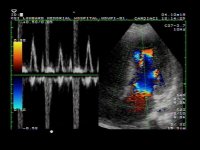

Szívultrahangos (Echokardiográfia) vizsgálat kapcsán a Medconnexus Gyógyászati Központban a szív, nagyerek, billentyűk funkció közbeni vizsgálatát végezzük rutinszerűen.

A világszínvonalú ultrahangkészüléknek köszönhetően már a legkisebb funkcionális eltérések is azonosíthatók.